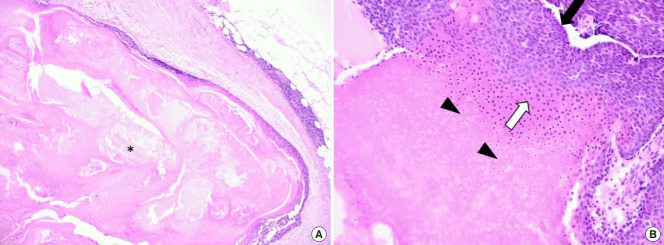

在全身麻醉下,通過皮膚切口有效切除腫塊(圖 4)。 腫塊位于淺表肌肉腱膜系統(tǒng)上方,經(jīng)測量為6.0×5.5×1.5 cm。 組織病理學(xué)檢查根據(jù)特征性發(fā)現(xiàn)診斷為毛母質(zhì)瘤,包括一個有包膜的腫瘤,中心區(qū)域有豐富的嗜酸性無核影細胞,周圍區(qū)域有藍色圓形基底樣細胞。 此外,觀察到多核巨細胞以及多灶性營養(yǎng)不良性鈣化和局灶性異物反應(yīng)(圖 5)。 患者康復(fù)無并發(fā)癥,隨訪 6 個月未見反復(fù)。

圖 5:顯微檢查顯示毛母質(zhì)瘤的典型特征。 (A) 在皮下組織中發(fā)現(xiàn)結(jié)節(jié)狀包膜腫瘤,中央壞死(星號)和瘤周輕度淋巴細胞浸潤(H&E,×40)。 (B) 腫瘤由厚纖維包膜下的外基底細胞和嗜堿性細胞(黑色箭頭)和中央嗜酸性細胞(白色箭頭)組成,具有毛母質(zhì)瘤特征的無核影細胞(箭頭)(H&E,×100)。